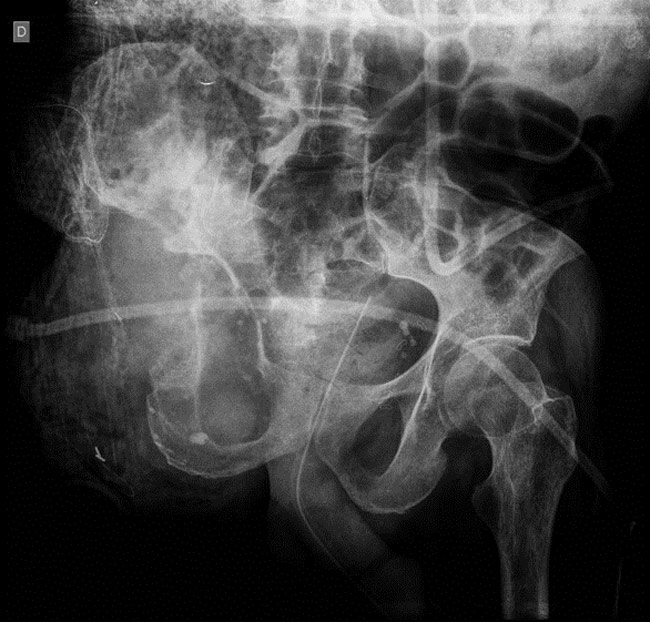

But... We noticed after removal of the drapes a massive knee instability that was not known before, and we asked for an x-ray.

A massive knee instability that was not known before

Internal fixation was impossible because there wasn’t enough bone distally. A Hinge TKR and a  bridging plate were fitted.

Internal fixation was impossible because there wasn’t enough bone distally